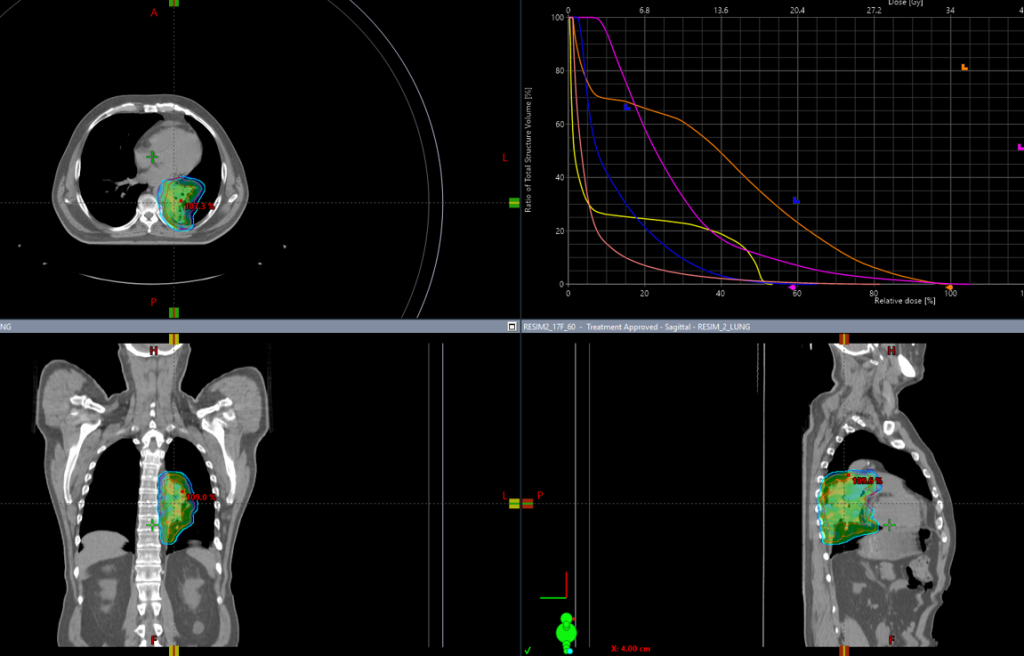

Пациенту рекомендован курс химиолучевой терапии на опухоль легкого и ПЭТ позитивные лимфатические узлы РОД 2Гр до СОД 60Гр на фоне еженедельного введения химиотерапии по схеме карбоплатин + паклитаксел

13.07.2022 выполнена КТ- топометрия органов грудной клетки с толщиной среза 2.5 мм.

Выполнено оконтуривание на КТ срезах объемов мишени (GTV,CTV,PTV) и всех органов риска

21.07.2022 был запланирован первый сеанс лечения

С 25.07.2022 начат курс лучевой терапии

На аппарате HALCYON с ежедневной KV-визуализацией

Одновременная химиотерапия по схеме паклитаксел+карбоплатин еженедельно

В Институте ядерной медицины мы регулярно используем ежедневную KV-визуализацию (компьютерная томография с коническим пучком) для более точной локализации опухоли и проведения прецизионной, то есть суперточной лучевой терапии. Особенно важна ежедневная визуализация при раке легкого, когда объем облучения может значительно и быстро изменяться, в результате резорбции опухоли или вследствие осложнений, например ателектаза. Так же ежедневная визуализация позволяет уменьшить отступ на погрешность в укладке пациента, тем самым снижает лучевую нагрузку на критические органы

с 21.07.2022 по 2.09.2022 проведен радикальный курс лучевой терапии на первичную опухоль легкого и ПЭТ позитивные лимфоузлы РОД 2 Гр СОД 60 Гр за 30 фракций с одновременной химиотерапией по схеме паклитаксел+карбоплатин, 4 введения еженедельно.